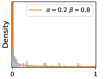

To model how different classifiers will respond to a given input , we assume that the prediction from classifier is sampled from a beta distribution that is characterized by two parameters by and . We further assume that is fixed to the same constant value for all ’s. Under this assumption, each input can be described by ( can be calculated since is fixed), easing further analysis. The Severity Level (SL) of the case represented by image can be characterized by the parameter . The larger the value of , the more severe the case of is. When and are close, the case is ambiguous as the distribution shifts towards being symmetric (i.e. signifying much disagreement among classifiers) rather than being one-sided (i.e. consensus among classifiers that is negative or positive). We provide a set of examples in Figure 2 and also Figure S.8 in the supplementary materials showing how the beta distribution can be used to capture diverse predictions given by an ensemble learner.

We conducted a case study on diagnosing diabetic retinopathy with ensembles of DL models. For benchmarking the performance of our ensemble-based solutions under the scheme described in Sec.3.3, we used two popular collections of diabetic retinopathy image data, the Kaggle Diabetic Retinopathy dataset [22] (hereafter referred to as “Kaggle-DR”) and the Messidor-2 dataset [23], each respectively consisting of and high resolution images. Diabetic retinopathy is graded into five SLs, as displayed in Figure 2. Following the problem setup used in previous papers [24], we trained models to distinguish the referable (SL2-4) cases from the non-referable ones (SL0 & SL1) (see Section B.1 for more detailed descriptions). We also tested our trained ensemble models on two o.o.d. image datasets (ImageNet [25] and CIFAR-10 [26]) to examine their capabilities of identifying o.o.d. inputs (see Section B in the supplementary materials).

In contrast, the MC-dropout method showed the worst overall performance among the three, as it can be seen from the high ratios of SL0 examples among the uncertain negatives in Figure 4. The histograms in Figure 2 provides another perspective to look into the phenomenon, where a decent proportion of MC-dropout model’s predictions on SL0 inputs entailed low confidence (far from 0 or 1), which from another angle explained why MC-dropout was less specific in terms of lower FNP; many no-DR inputs (i.e. SL0) were erroneously assigned high uncertainty by MC-dropout models.

It is still an open question why the evaluated MC-dropout networks signaled relatively high uncertainty on SL0 & SL3 & SL4 data that are less likely to be ambiguous. We conjecture that much of the “uncertainty” indicated by disagreement among test-time dropout samples actually reflects the stochastic nature of dropout networks rather than the real decision uncertainty associated with the data. It is worth noting that the MC-dropout model we evaluated was not weak per se; they all achieved above Area Under Curve (AUC) scores on test sets. The weakness of individual test-time samples (which explains their low-confidence predictions on SL0 & SL3 & SL4) might have been hidden when they are aggregated into an ensemble—a well-known advantage of ensemble learning. Our results suggested that the uncertainty information given by implicit ensemble methods such as MC-dropout and TTA might not be as reliable as that from explicit ensemble approaches (e.g., stacking ensembles). Similar findings on MC-dropout can be found in some previous papers [1].